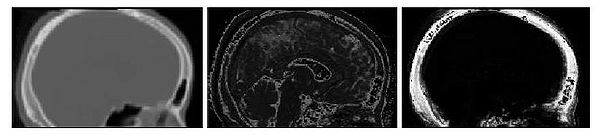

Results of the segmentation of bone from structural MR for a representative subject is shown in Fig. 6. The

CT shown on the left can be easily thresholded to segment bone from air and

soft tissue. The results of using the intensity and atlas-

based classifiers are shown in the middle and right images, respectively. While the intensity classifier has some success in

segmenting MR into tissue/air classes, it is much less effective in segmenting

bone. Inspection of the the atlas-based segmentation, however, shows good general agreement with the CT, with a dice score of 0.780 for

this subject.